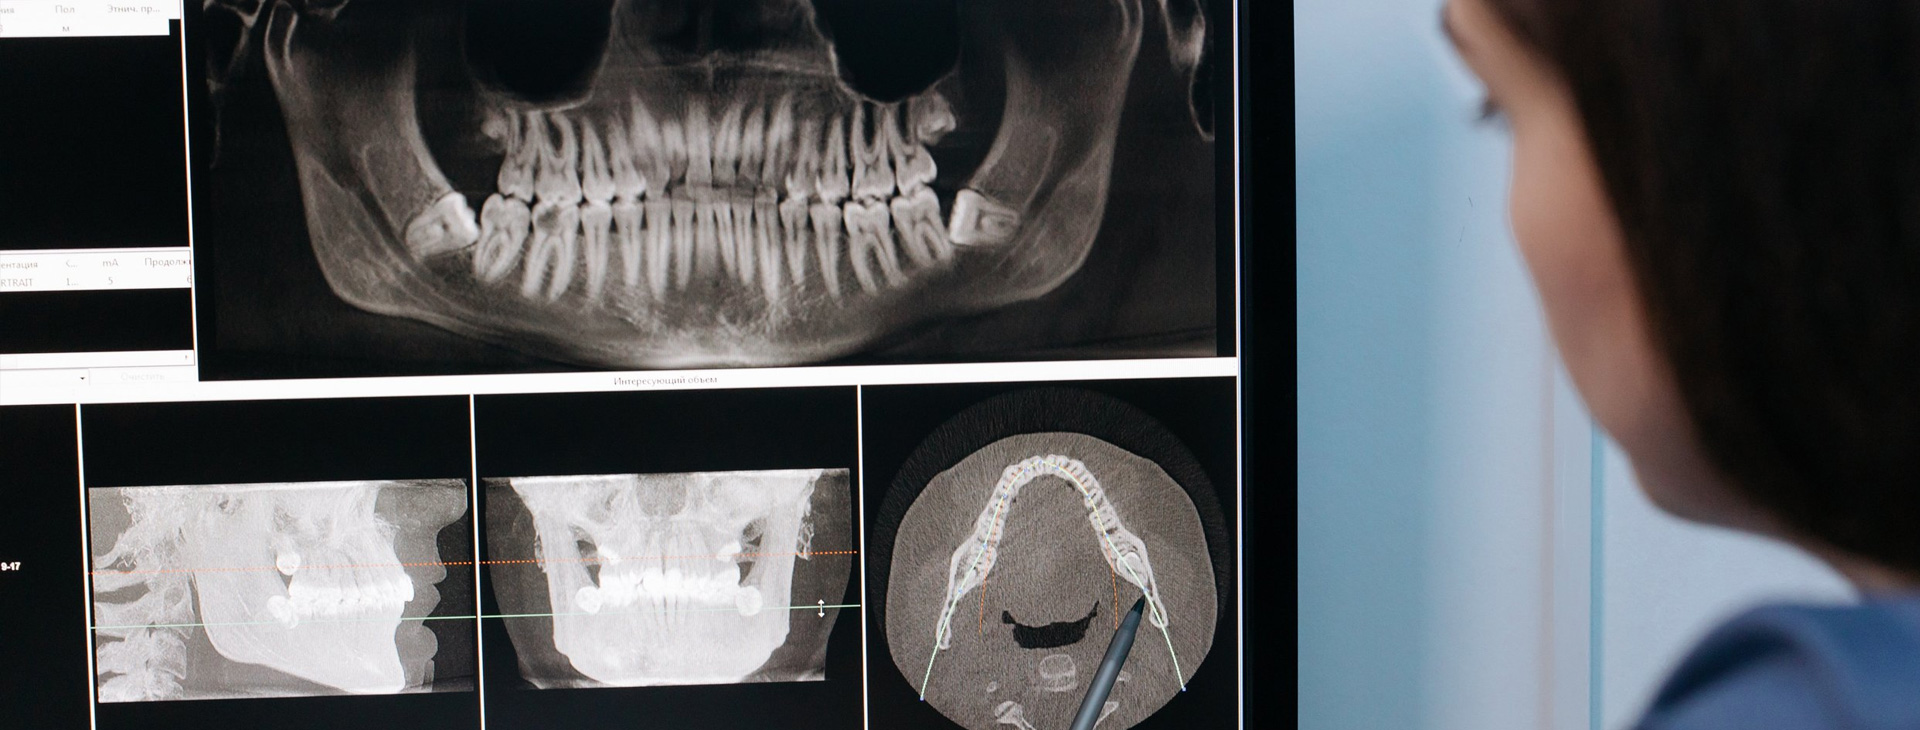

Rayos X Dentales en Puebla

Equipo especializado, tecnología 100% digital avanzada

Rayos X Digitales

Equipo especializado con mayor nitidez y contraste permitiendo apreciar mejor los detalles y densidades.